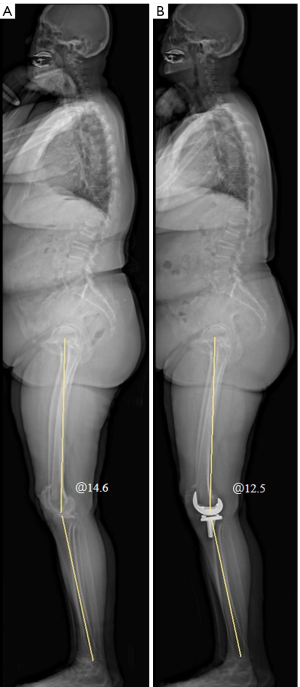

Measurement of spino-pelvic coronal parameters

Two spino-pelvic coronal parameters were measured in EOS anteroposterior images, including PO and C7-central sacral line (C7-CSL) (Figure 2A,2B). PO was the angle between the line connecting the topmost points of the iliac crests and the horizontal line. If the left iliac crest was higher than the right, the angle was recorded as a positive value (+) (6). C7-CSL was the horizontal distance between the plumb line through the center of the C7 vertebra and the midline of the sacrum. If the plumb line was to the right of the sacral midline, it was recorded as a positive value (+) (6). The difference between preoperative and postoperative values of these parameters was represented as delta (Δ).

HKA

HKA was measured on EOS anteroposterior images. HKA was defined as the acute angle formed by the mechanical axes of the femur and tibia in the coronal plane, with varus angles recorded as positive values (+) (Figure 2) (6). ΔHKA was the difference between preoperative and postoperative values.

KFA

KFA was measured using lateral images from the EOS system. KFA is defined as the acute angle formed by the mechanical axes of the femur and tibia in the sagittal plane, with flexion angles noted as positive values (+) (Figure 3A) (7). ΔKFA was the difference between the preoperative and postoperative values.

There were 70 patients, 26 males and 44 females, with an average age of 68.7±5.1 years (54–79 years). There were 35 cases involving the left knee and 35 involving the right knee. The average BMI was 27.5±3.7 kg/m2 (range, 22.2–37.5 kg/m2). The KFA values (7.0°±3.2°) after TKA decreased compared to those (15.4°±6.8°) before TKA (Figure 3B). Groups A and B had 39 and 31 patients, respectively (Figure 4).